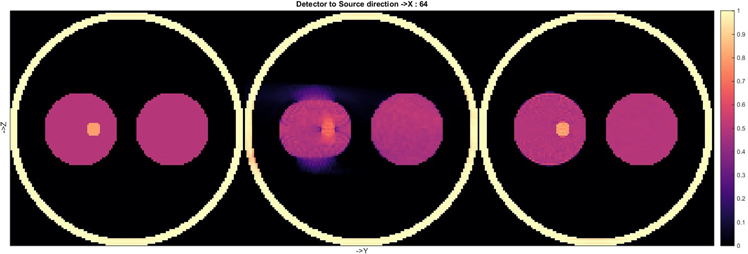

Standard image High-resolution imageThe success of phase-space tomography in accelerators inspired a study at CERN that aims to use the same technique to improve motion compensation in medical imaging. To test the approach, a proof of principle was created using a simple thorax-like phantom, which was mimicked in computer simulations by a collection of spheres. Three reconstructions made using the new method, called the simultaneous algebraic reconstruction technique (SART), are shown in figure 12.

Figure 12. Three reconstructions of the same phantom using SART. The third reconstruction (far right) shows that the image is effectively 'frozen' at the starting point of the cyclic motion, demonstrating the success of the motion compensation algorithm. The density (colour) scale is in arbitrary units.

Standard image High-resolution imageAll elements of the phantom were completely static for the first reconstruction, while the second one showed the expected degradation when the data were generated when the left 'lung' was moving (without deformation) during the simulated CBCT scan. In this case the motion was assumed to be sinusoidal, with an amplitude of 1.25 times the radius of the 'tumour', and it was only in the vertical direction for the reconstructed plane shown. The third image was produced from the same dynamic dataset as the second one, using the same SART algorithm, but the geometry of the reconstructed image was modified as a function of time while the data were being recorded. This image clearly shows that this technique is capable of 'freezing' the image before the onset of the cyclic motion, thus compensating for the known movement. The entire dataset was used in each reconstruction, and it is a feature of the CERN algorithm that the motion is not constrained to be cyclic, which means that any type of movement can be compensated for.